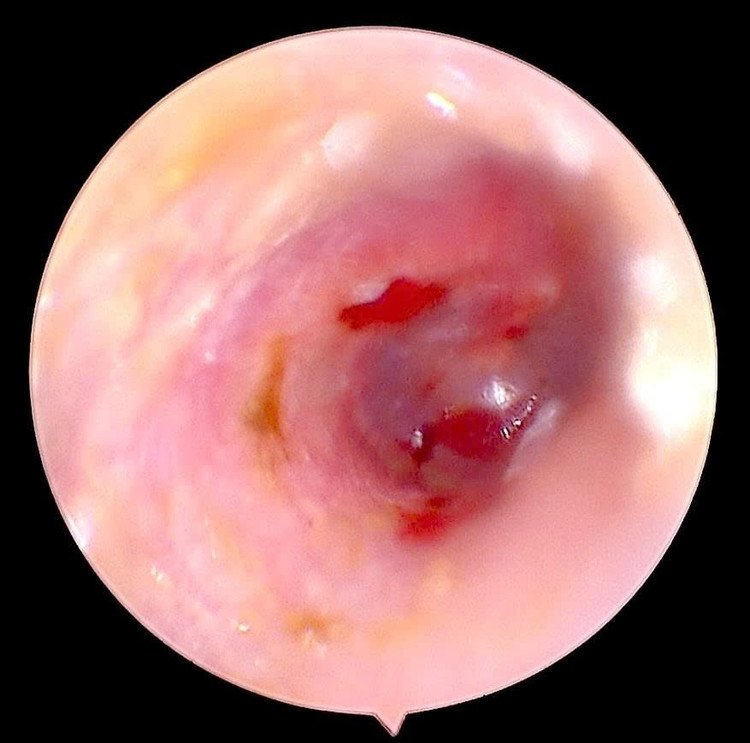

Qua thăm khám và nội soi tai, bác sĩ phát hiện một dị vật là côn trùng còn nguyên vẹn, kích thước khoảng 0,5 cm, nằm sâu trong ống tai phải. Côn trùng di chuyển trong tai khiến màng nhĩ tổn thương, sưng nề và xung huyết, gây cảm giác đau nhói và ù tai liên tục.

Côn trùng chui trong ống tai gây tổn thương - Ảnh BVCC

Ngay sau khi xác định vị trí dị vật, bác sĩ đã tiến hành lấy dị vật dưới nội soi với thao tác cẩn trọng, an toàn, tránh làm tổn thương thêm màng nhĩ.